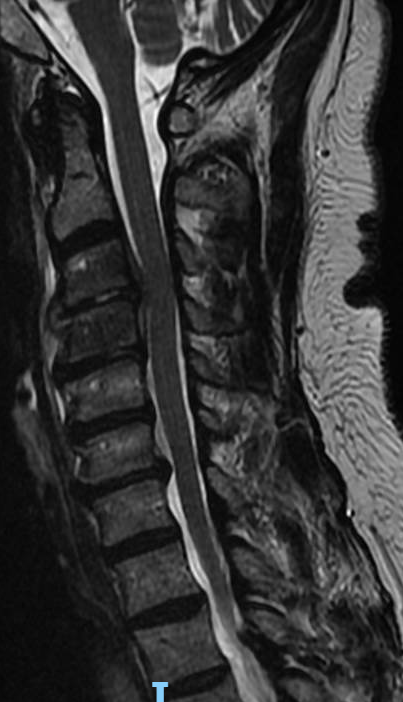

Severe malalignment case: Performed T12-S1/Pelvis posterior instrumentation, TLIF at L5-S1 & L5 PSO. No anterior approach on vascular team's advice. Patient now stands upright & grateful. #SpineSurgery #MedTwitter #scoliosis #flatback #HarringtonRods #ScoliosisWarrior

10

50s patient with severe malalignment. How would you treat this surgically? Nnee compensation in coronal and sagittal planes. Options: Multisegment instrumentation, TLIF/ALIF/OLIF, PSO, refer to another surgeon? Thoughts? #neurosurgery #spine #scoliosis #flatback #harringtonrods